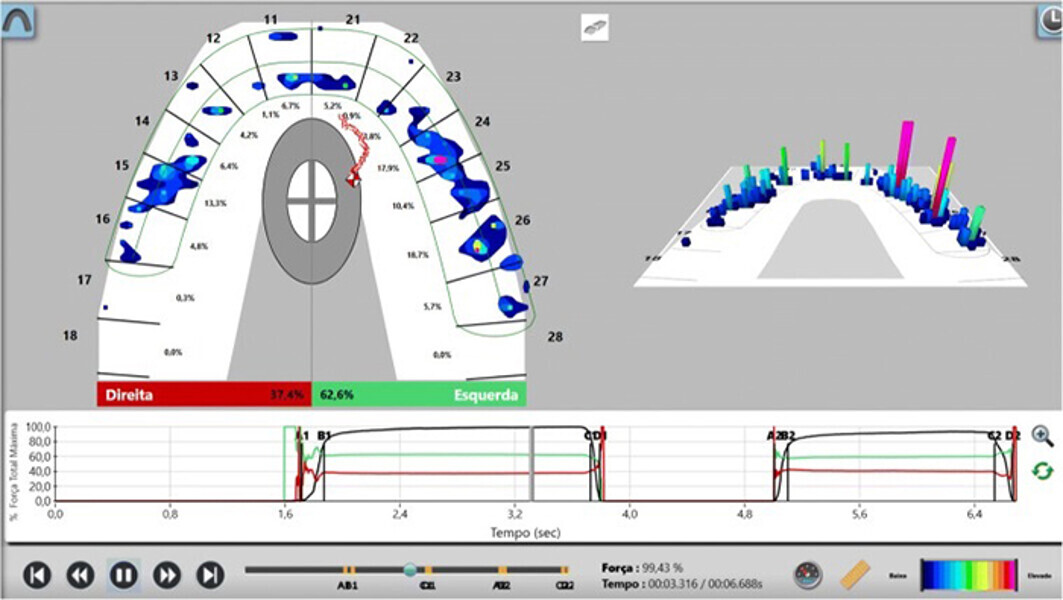

Fig. 16. Confirmación de la oclusión mediante tecnología T-scan.